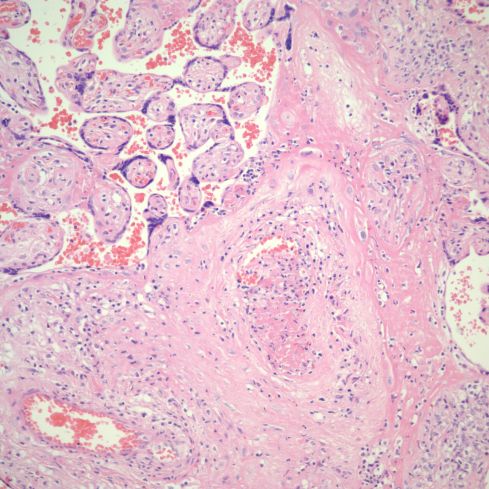

Fig 28) There is core of villi enmeshed in a basophilic matrix surrounded by villi demonstrating VUE. The rectangle is shown at higher magnification in the next figure. (H&E, 4X)

Fig 29) At higher magnification, the basophilic matrix can be seen to be similar to the fibrinous fibrinoid matrix of perivillous fibrinoid deposition with the addition of numerous inflammatory nuclei from perivillus and subsyncytial inflammatory cells. (H&E, 20x)